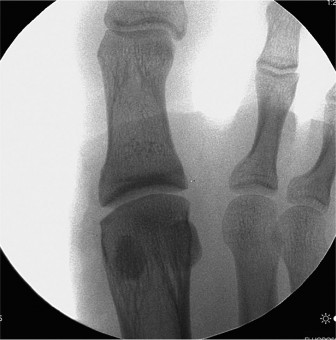

Standard weight-bearing anteroposterior, lateral, and oblique radiographs of the foot were obtained. The anteroposterior view demonstrated subtle widening of the second metatarsophalangeal joint space and early medial deviation of the second digit. The intermetatarsal angle between the first and second rays was within normal limits, but the distance between the second and third metatarsal heads appeared slightly increased.

On the lateral weight-bearing projection, the dorsal subluxation of the second proximal phalanx relative to the metatarsal head was clearly visualized, confirming the clinical observation of the incipient hammertoe deformity. A careful review for a Fleck sign, representing a small cortical avulsion fracture from the base of the proximal phalanx, was negative. The lack of overt fracture highlights the purely soft-tissue nature of the failure in this specific athlete.